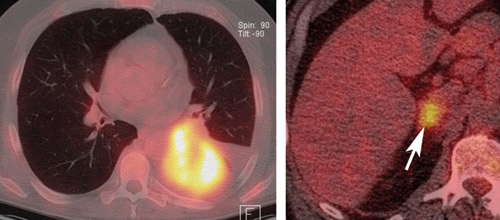

En 57 år gammel mann med adenokarsinom i venstre lunges underlapp ble undersøkt med 18F-fluoro-2-deoksyglukose (FDG)-PET kombinert med CT i samme seanse for stadieinndeling av tumoren. FDG er det vanligste sporstoffet som benyttes i PET og akkumuleres gjennom en sukkerforbrenningsprosess i cellene og gjenspeiler cellenes energibehov.

Bildet til venstre viser høyt opptak i tumor (gul/hvitt), men det er ikke innvekst i mediastinum eller store kar, slik at tumoren i seg selv er operabel.

Bildet til høyre viser metastase i høyre binyre (pil) og flere steder i skjelettet (ikke vist) gjør at pasienten ikke er operabel (stadium T2bN0M1b), men i stedet er kandidat for ikke-kirurgisk onkologisk behandling.

PET/CT er egnet for stadieinndeling av lungecancer, inklusiv målrettet invasiv diagnostikk av mediastinum. Ved PET/CT kan man skille metastaser fra benigne lesjoner i binyrer og se okkulte fjernmetastaser hos 5 – 29 % av pasientene der konvensjonell stadieinndeling ikke har vist dette. Binyrer er et av de vanligste organene for fjernmetastasering fra lungecancer.